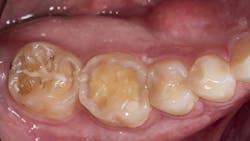

A 27-year-old patient was referred to me due to discomfort associated with dentinal hypersensitivity secondary to erosion on his posterior teeth (figure 1 above: Initial presentation. Note the exposed dentin due to erosion). His former dentist suggested crown lengthening due to inadequate space for full-coverage crowns.

After a thorough evaluation of his clinical presentation, radiographs, and intraoral scan, it was evident that the discomfort was due to exposed dentin. The intraoral scan confirmed there was adequate interocclusal space to restore the eroded tooth structure with a minimally invasive approach (figure 2). All options were reviewed with the patient, and it was mutually agreed upon to address his chief complaint in this manner. Proper isolation is critical for reliable bonding.